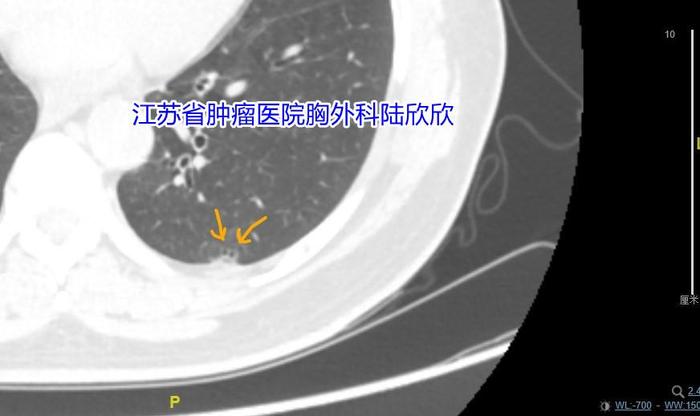

十五、长翅膀的哑铃形磨玻璃结节

可见2023年的哑铃形磨玻璃结节最大径41毫米,结节腹侧的磨玻璃成分看起来像是一个翅膀。病理是浸润性腺癌,亚型是腺泡亚型和贴壁生长亚型2020年时这个磨玻璃结节最大径21毫米,可惜当时的医生没有认出是恶性病变,误认为是炎性病变。